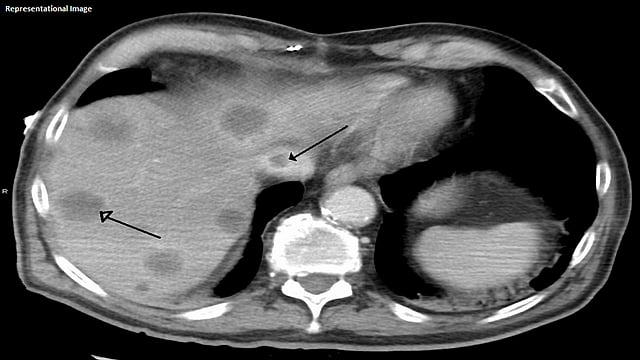

'बड छिआरी सिन्ड्रोम' आजारात यकृताकडून हृदयाला रक्तपुरवठा करणाऱ्या नसा अतिशय बारीक होत जातात. त्यामुळे रक्तपुरवठ्याच्या कार्यात अडथळा निर्माण होतो. परिणामी रुग्णाचे पोट फुगते, शरीराच्या काही भागांवर सूज येते. या आजारामुळे माझ्या शरीरातील शुद्ध रक्त हृदयापर्यंत जात नसून, यकृताचे कार्यही त्यामुळे बिघडले आहे.  या आजारामध्ये यकृत प्रत्यारोपण हा शेवटचा पर्याय असल्याचे यकृतप्रत्यारोपण तज्ज्ञ डॉक्टरांचे स्पष्ट मत आहे.